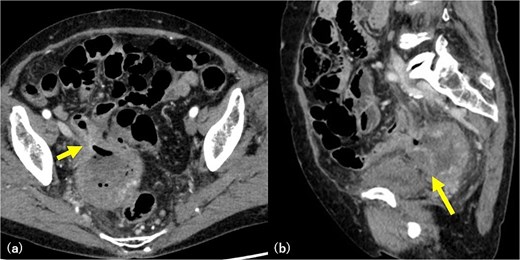

Transvaginal ultrasonography at 1 and 6 months showed no change. Sixteen months postoperatively, she presented with abdominal pain. CT revealed a fistula with the small intestine and also demonstrated abscess formation between the residual mass and small intestine, with an abscess between the mass and bladder (Fig. 4), accompanied by elevated inflammatory markers. As repeat excision was considered high risk, surgical management focused on controlling inflammation by eliminating intestinal communication. A diverting double-barrel loop ileostomy was therefore planned laparoscopically. A trocar was first placed at the umbilicus for the laparoscope, and additional trocars were placed in the right lateral and lower abdomens. Severe adhesions were encountered, necessitating the placement of additional trocars in the left lateral and lower abdomens. The small intestine was looped and clustered on the right pelvic floor; however, the gossypiboma could not be identified. The terminal ileum in the caecum was identified, and the fistula site was determined to be ~17 cm proximal to the ileocecal junction. A double-barrel stoma was created 10 cm proximal to the fistula site in the right lower abdomen (Fig. 5). After confirming her ability to manage the stoma and tolerate oral intake, she was discharged on post-operative Day 24. To date, no recurrence of the pelvic inflammation has been reported. The overall clinical course of the present case is summarized in the timeline (Fig. 6).

Abdominal CT imaging. Axial CT image showing intralesional air within the gossypiboma, indicating communication with the small intestine (arrow) (a). Sagittal CT image demonstrating fluid collection between the mass and the bladder, consistent with abscess formation secondary to rupture (arrow) (b).